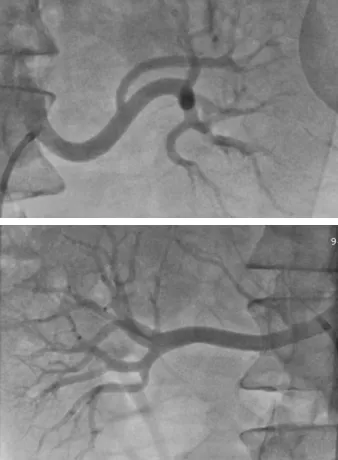

手术过程中,夏文豪教授在精准影像引导下,细致识别每一支细小分支,严格遵循应消尽消原则,对符合要求的肾动脉及分支进行全面、规范、安全的消融,全程操作平稳流畅,顺利完成高难度RDN手术。

▲肾动脉造影提示双侧肾动脉迂曲